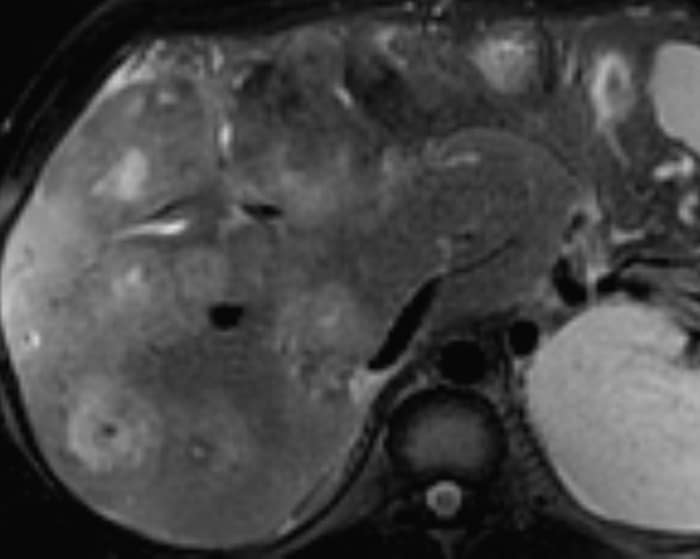

Di căn gan

» Thông tin: Nam giới – 37 tuổi.

» Lâm sàng: Tiền sử K đại tràng.